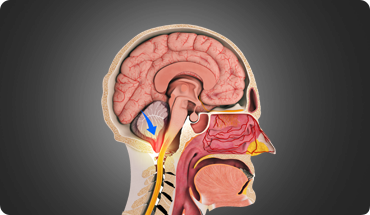

NeurosurgeryEndoscopic endonasal approach (EEA) is a minimally invasive surgical technique that allows your surgeon to treat tissue damage and tumours near the spine or brain by utilising an endoscope placed through the nose and sinuses.

Pituitary tumours are abnormal growths within the pituitary gland, a small gland located near the base of the brain. Pituitary tumours can be either functioning or non-functioning. Functioning tumours secrete pituitary hormones that can lead to a clinical syndrome, while non-functioning tumours are those that can cause a syndrome by not secreting pituitary hormones.